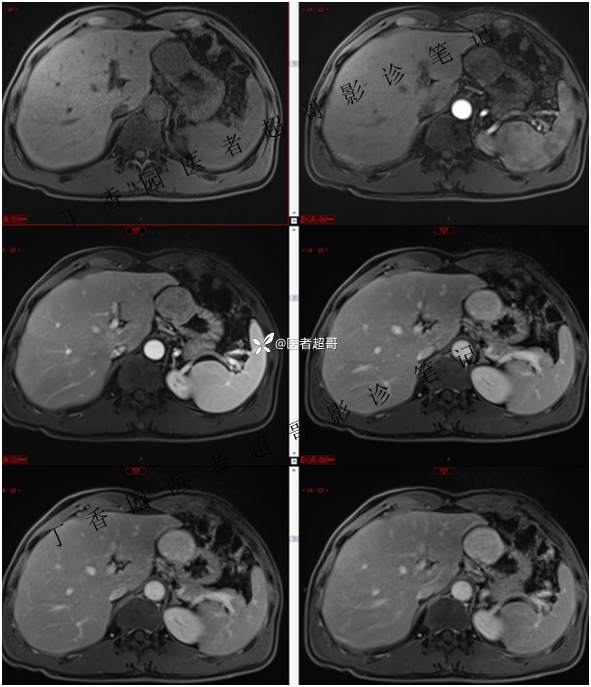

肝胃间隙肿瘤,间质瘤?平滑肌瘤?还是鞘瘤?有结果,请分析!

主 诉:查体发现肝占位3天。

现病史:患者于3天前查体行肝胆脾胰肾彩超示肝内实性占位,无恶心、呕吐,无发热、寒战,无腹胀、腹泻,进一步于医院行上腹部CT增强示:肝胃交界处肿块。未行特殊治疗。今患者为求进一步治疗,来我院就诊,门诊以“肝占位性病变”收入院。患者自发病以来,神志清,精神可,饮食睡眠可,二便可,体重近期未见明显变化。